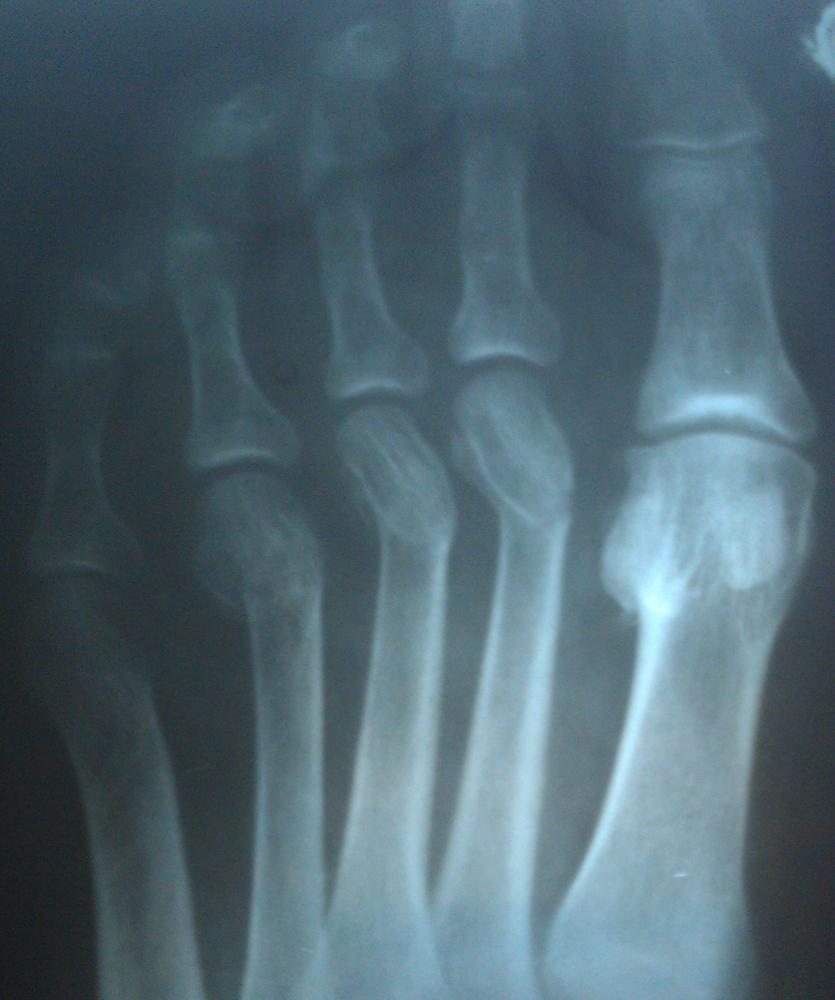

В общем есть рентгеновский снимок пальцев ноги.

Где делали рентген, сказали - сломаны 2,3,4 палец.

Травматолог посмотрел снимок - сказал, ушиб, переломы очень старые.

Кому верить? Гипс не поставили, просто дома в покое быть назначили (не мне).

Я так посмотрел другие рентгеновские снимки переломов пальцев ног в интернете - вроде нет переломов никаких.